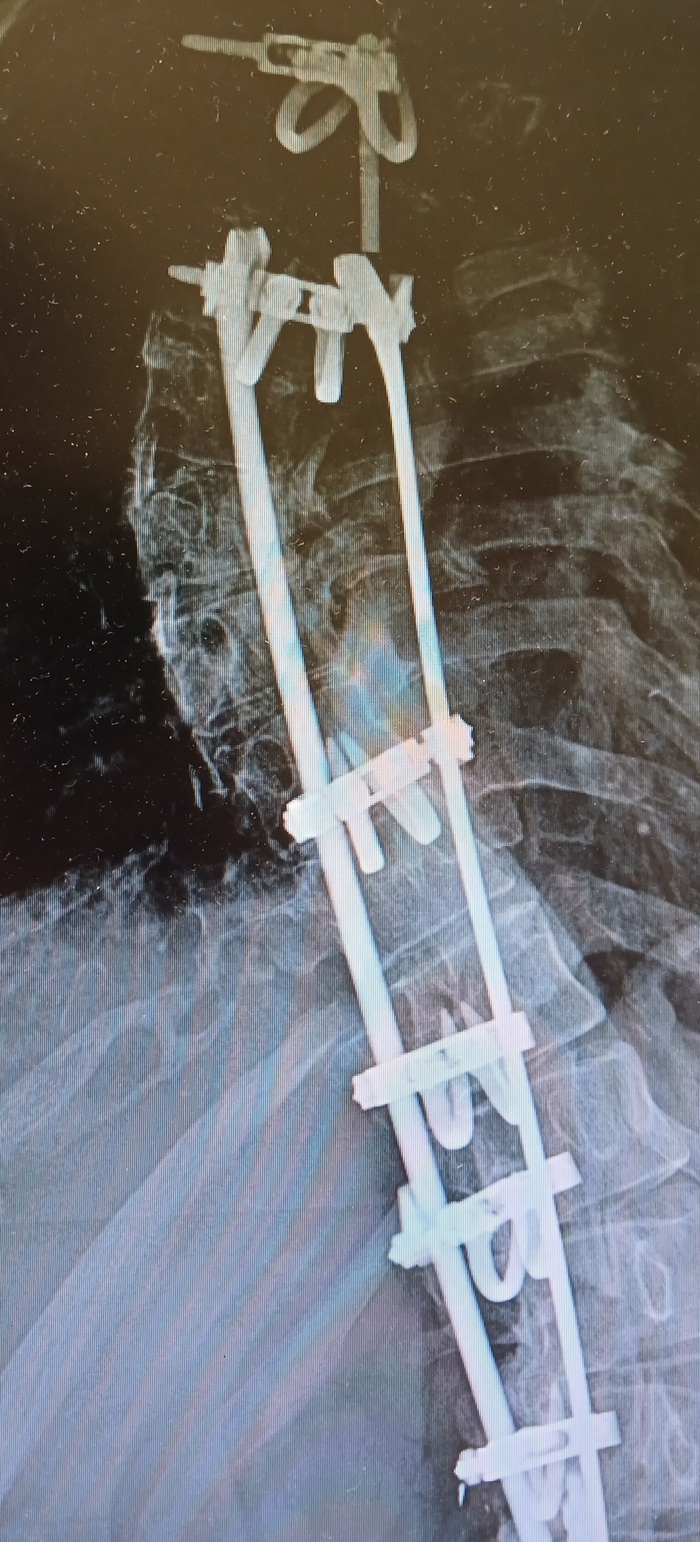

А, ну так вот. В 15 лет (2006 год) меня прооперировали, поставили титановую конструкцию. Стоила эта хрень 33700. Как щас помню.

Думаете, это все? Хуюшки сказал заюшка. Через год (2007) выяснилось, что мне неправильно поставили крючок. Пришлось переделывать. Когда только-только все зажило, и я едва смогла нормально дышать, выясняется такое... Отрицание, гнев, торг, депрессия – все было. Очень тяжело далось мне это, родителям так и подавно. Но ничего, поправили. Получилось как-то так

Как шмогли. Но стало лучше, ибо страшно мешал, а потом норм. Фото новое, но с тех пор ничего не менялось

Проходит 2 славных года. И что же? Я ломаю верхнюю шпильку! Титановую! Ай да я, ай да рубль мне! Но получила я пиздов ото всех, особенно от врача😁

Это фото со снимка, но не 2009, 2014 год, по традиции, сделано на тапок

Внимание на верхушку, она поехала, видите? Грубо говоря, негерметично стоит

И вот я в РНИИТО им.Вредена. 2 декабря успешно прооперировали. Вытащили все, кроме 2 крючков, уж больно плотно вросли в позвонки. На место дырок поставили искусственную кость в виде гранул. На все про все ушло 3 часа. Плюсом почистили ткани, врач сказал, из-за реакции на металл все внутри было чёрное (как моя душа). Поэтому был риск инифицирования, но все обошлось

Вот они 2 штучки, они со мной навечно. Я сгнию, они останутся 😁 Снимок со стороны груди